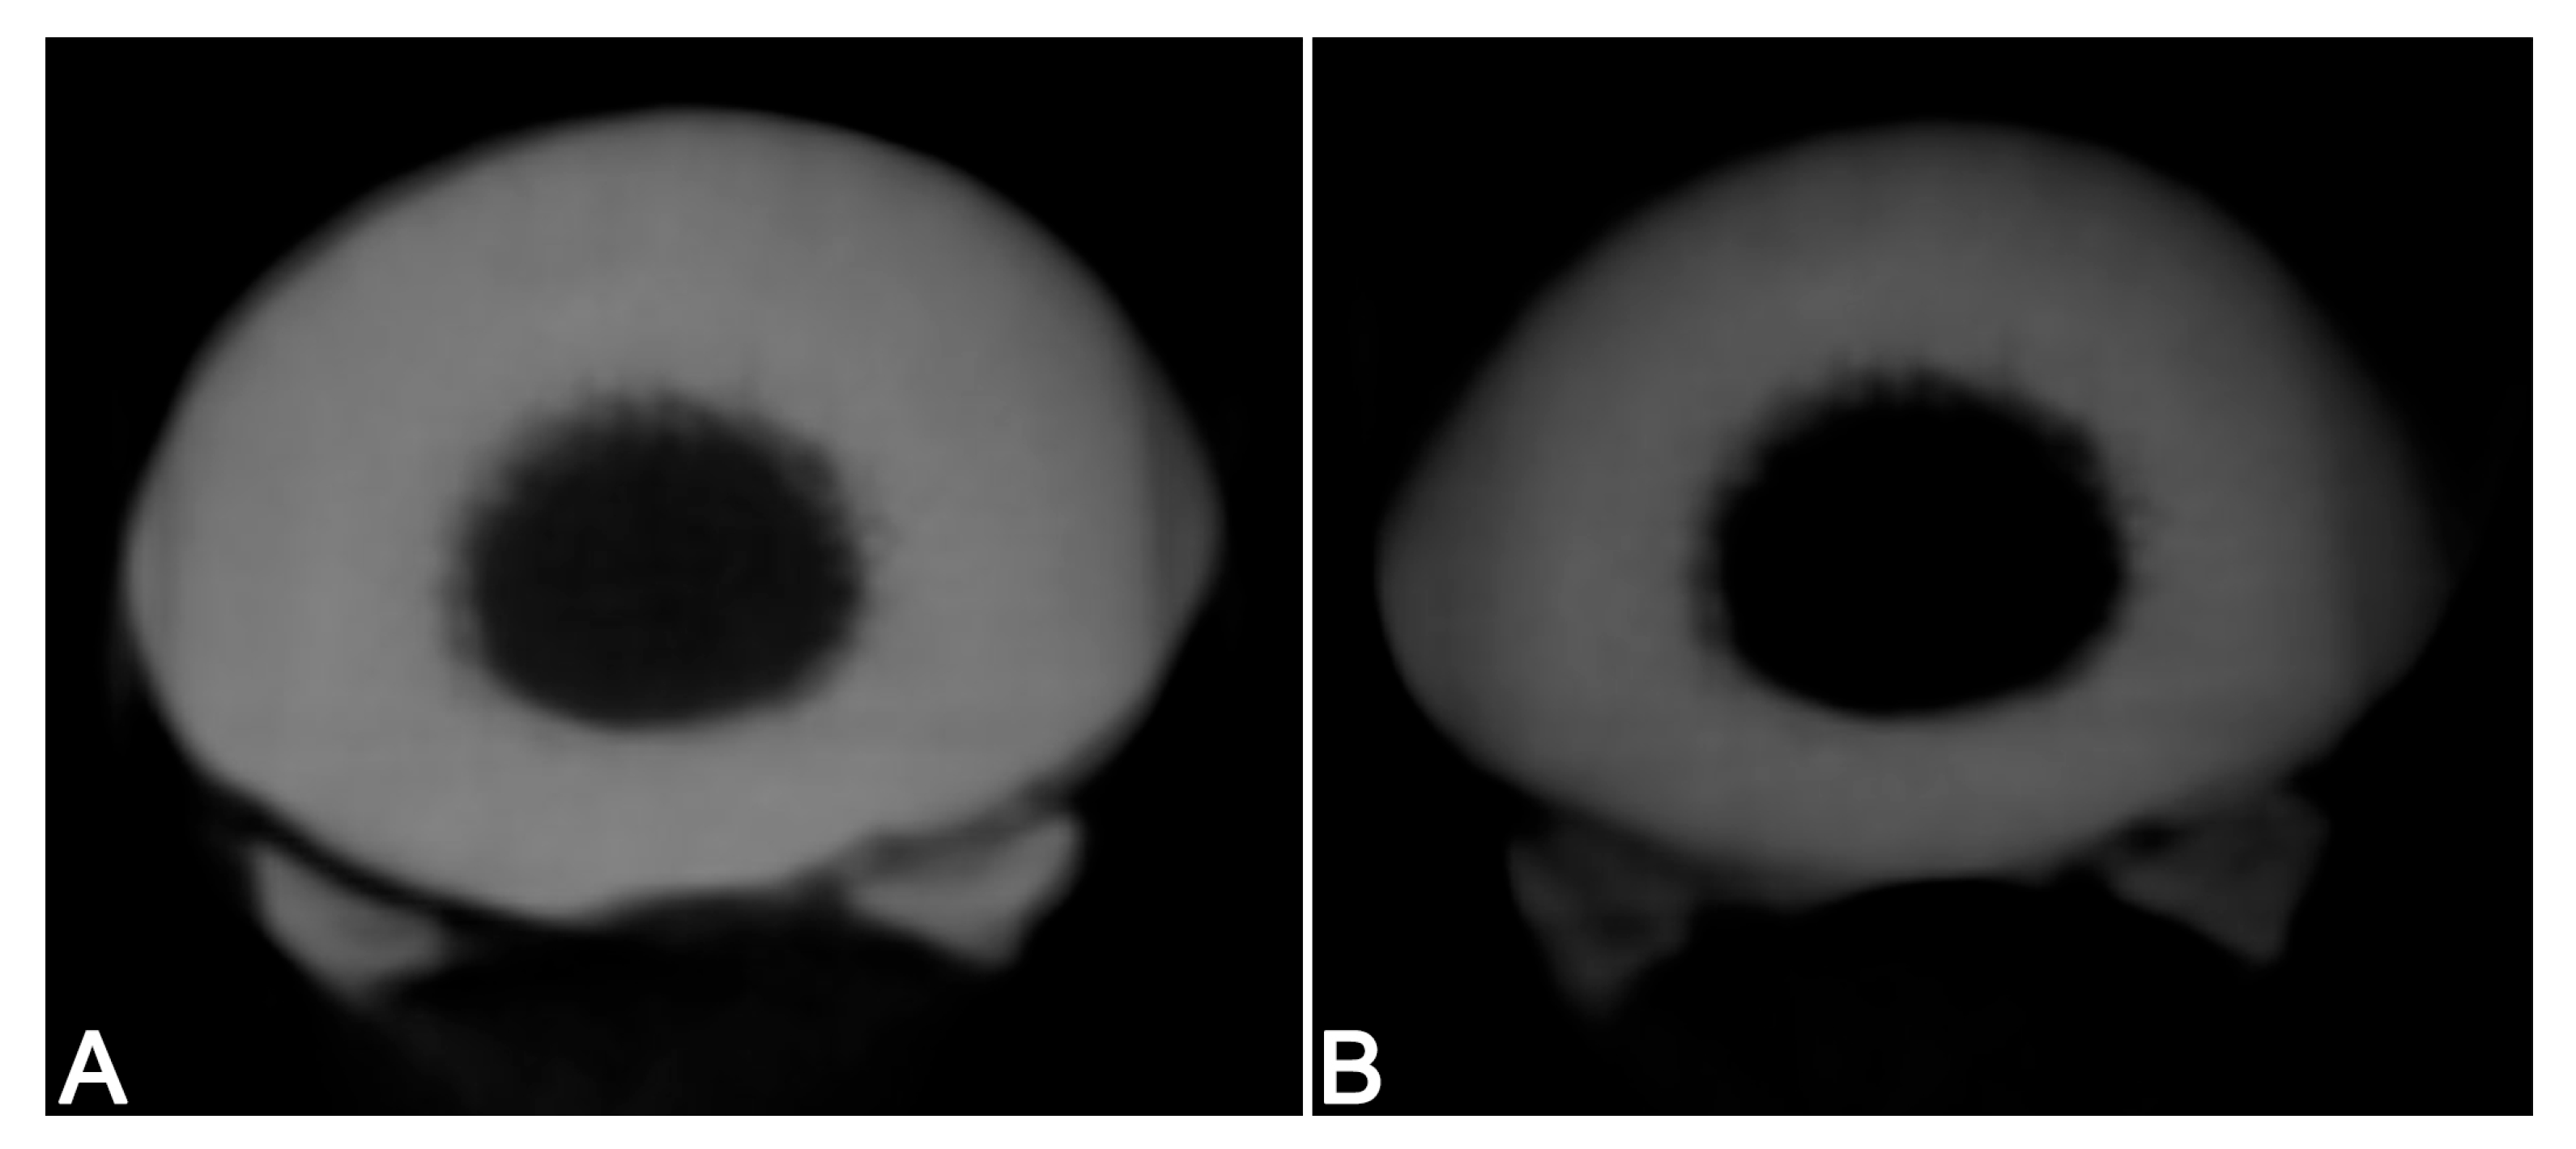

3.2. Clinical Case–Visual Image Quality Assessment